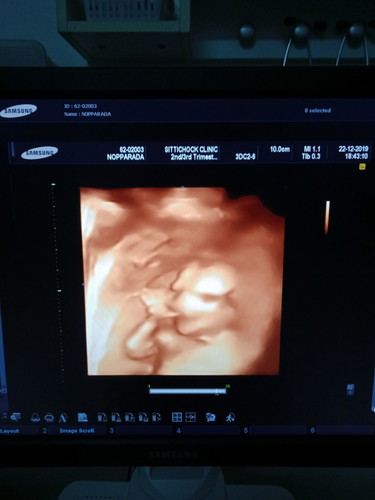

นอนดูดนิ้วใหญ่เลยนะลูกชายอิแม่ 15w3d แล้วคับ ❤️